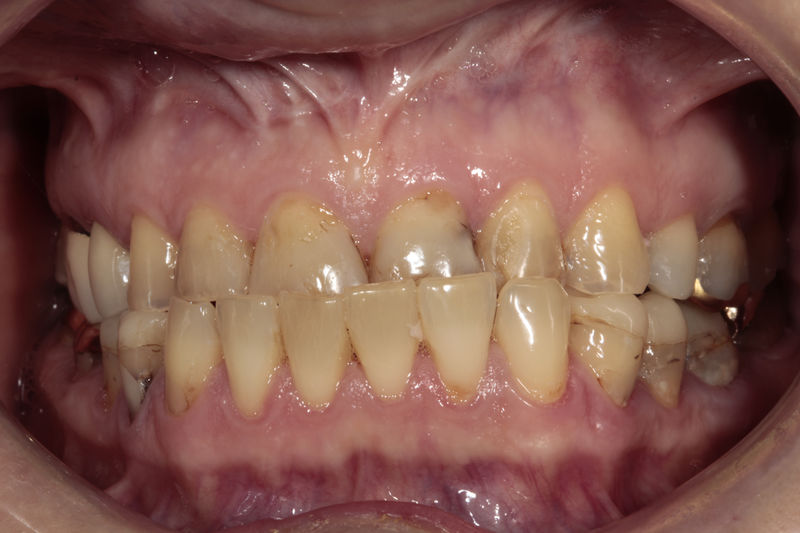

Implantes, ortodoncia y coronas.